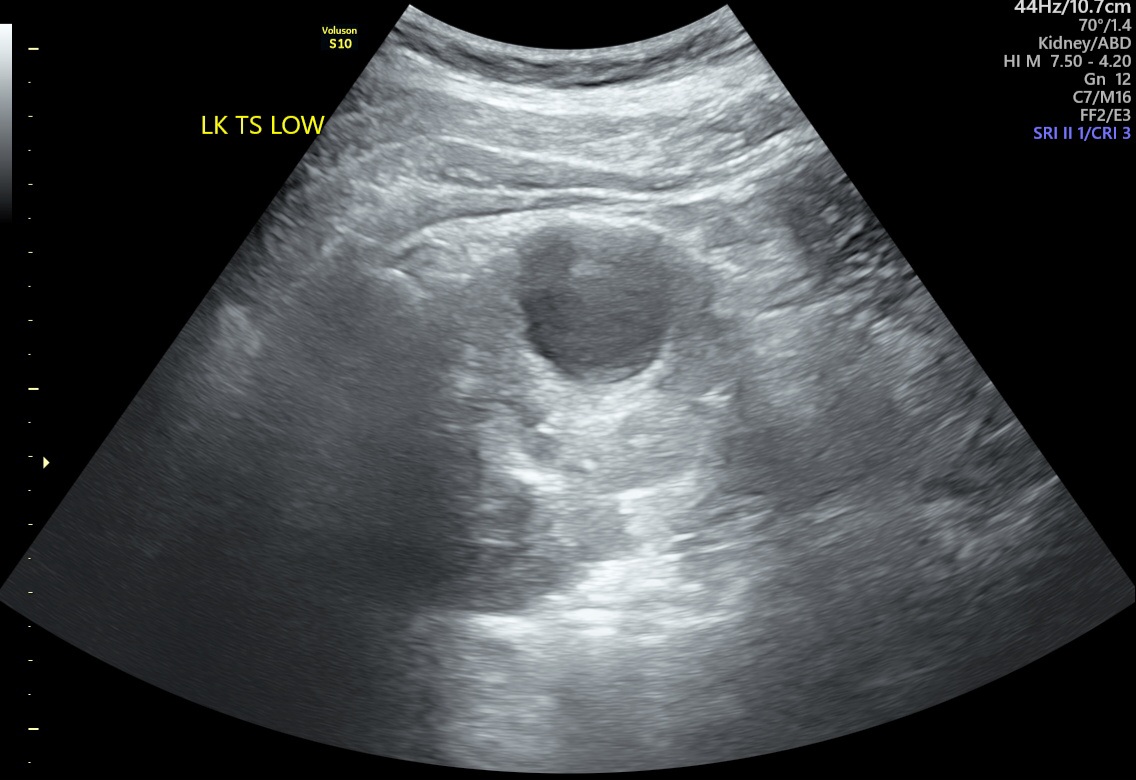

Czy mógłby ktoś mi powiedzieć czy 'infekcja cysty' to poprawna interpretacja załączonego USG?

Załączniki